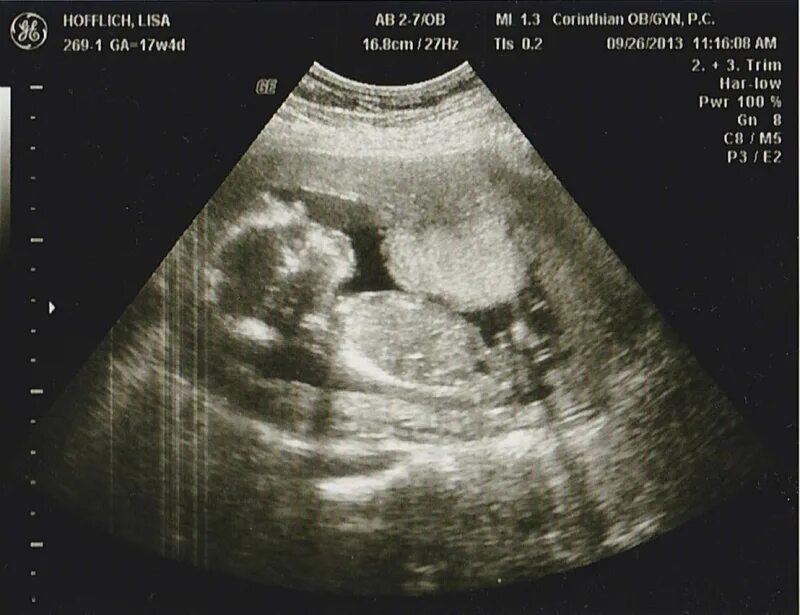

Тонус на ранних сроках форум